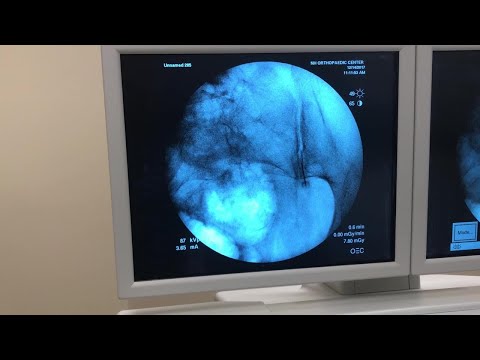

Intra-Articular Injection of the Sacroiliac Joint Under Fluoroscopic Guidance

Demonstrates fluoroscopy-guided SI joint injection technique including joint line identification, needle placement, and arthrogram confirmation.